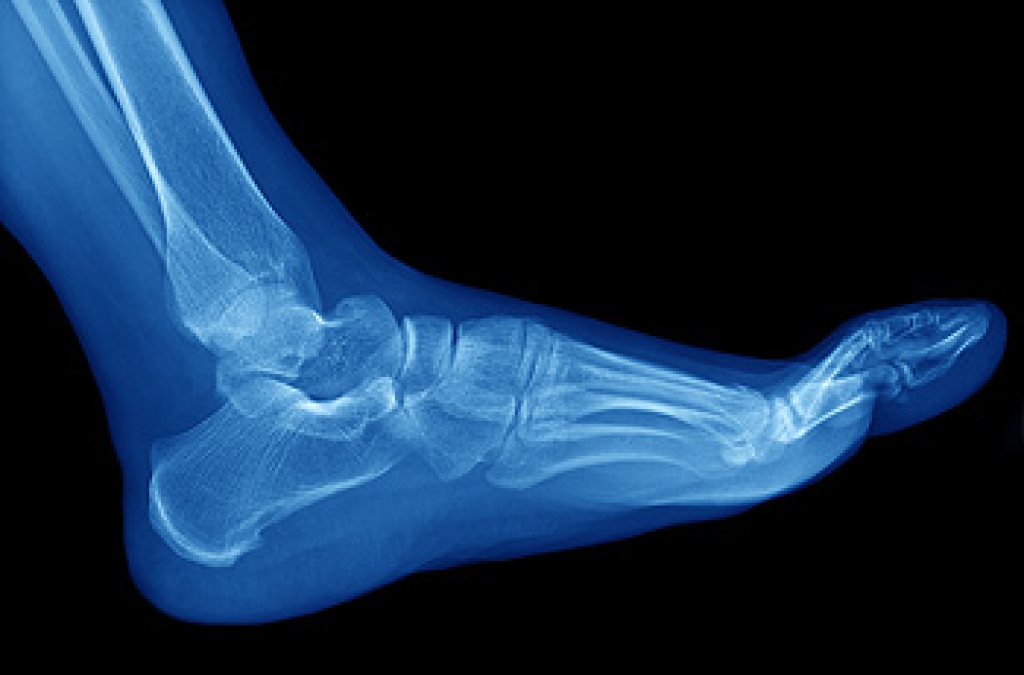

Cracked Heels

Cracked heels appear unappealing and can make it harder for you walk around in sandals. Aside from looking unpleasant, cracked heels can also tear stockings, socks, and wear out your shoes. There are several methods to help restore a cracked heel and prevent further damage.